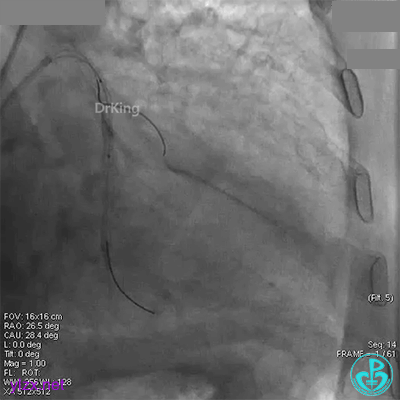

近端串联植入3.5×23mm支架后造影,前向血流没有恢复,患者感胸痛明显。

经刺破球囊冠脉内推注硝普钠后血流恢复2级,远端分支血管没有充分显影。